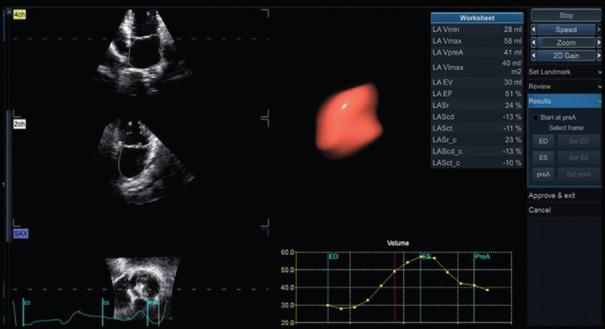

The left atrium (LA) is a vital component of the cardiovascular system, playing a crucial role in cardiac function. It acts as a reservoir, conduit, and contractile chamber, contributing to optimal left ventricle (LV) filling and cardiac output. Abnormalities in LA function have been associated with various cardiovascular conditions, including heart failure, atrial fibrillation, valvular heart disease, and hypertension. Elevated left ventricular filling pressures resulting from impaired LA function can lead to diastolic dysfunction and increase the risk of adverse cardiovascular events. Understanding the relationship between LA function and LV filling pressures is crucial for comprehending the pathophysiology of cardiovascular diseases and guiding clinical management strategies. This article provides an overview of the anatomy and physiology of the LA, discusses the role of LA mechanics in maintaining normal cardiac function, highlights the clinical implications of elevated filling pressures, and explores diagnostic methods for assessing LA function and filling pressures. Furthermore, it discusses the prognostic implications and potential therapeutic approaches for managing patients with abnormal LA function and elevated filling pressure. Continued research and clinical focus on left atrial function are necessary to improve diagnostic accuracy, prognostic assessment, and treatment strategies in cardiovascular diseases. It will explore the importance of assessing LA function as a marker of cardiac performance and evaluate its implications for clinical practice. In accordance with rigorous scientific methodology, our search encompassed PubMed database. We selected articles deemed pertinent to our subject matter. Subsequently, we extracted and synthesized the salient contents, capturing the essence of each selected article.